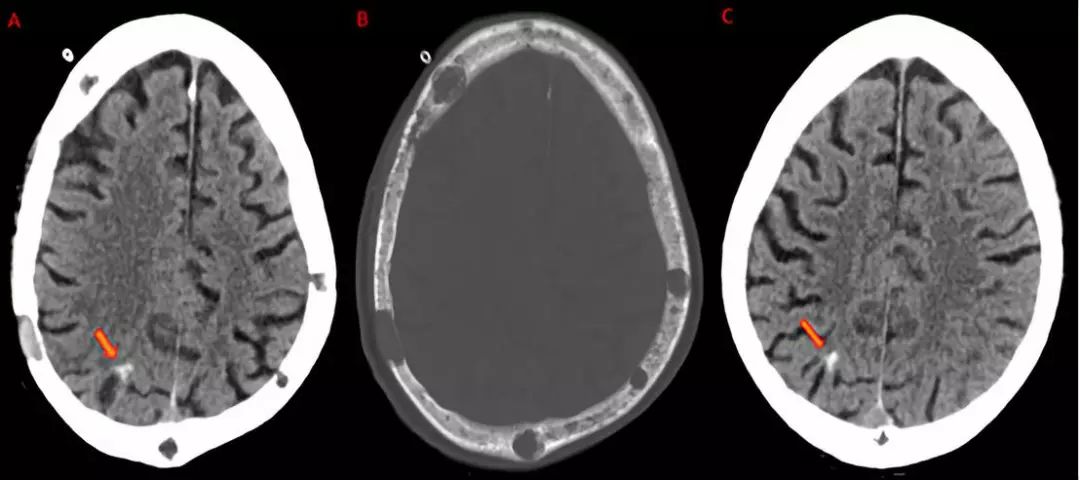

1.成年发病的白质脑病合并轴索球样变和颗粒样胶质细胞(adult-onset leukoencephalopathy with axonalspheroids and pigmented glia,ALSP)

包括临床表型和病理特点十分相似的2种疾病:遗传性弥漫性白质脑病合并轴索球样变(hereditary diffuse leukoencephalopathy with spheroids,HDLS)和家族性颗粒样细胞白质脑病(pigmentary leukodystrophy,POLD)。临床症状包括性格行为改变、精神症状、进行性认知功能衰退、运动障碍如非对称性帕金森综合征、皮层功能障碍等。典型的钙化特征是脑室周围小钙化灶。其他影像表现有:早期双侧非对称性局限性T2/Flair高信号,以额叶或额顶叶为著,主要累及深部,皮质下脑室周围白质束。可有皮质脊髓束受累,弥漫性脑萎缩,脑室扩大,伴胼胝体发育不良及异常信号。